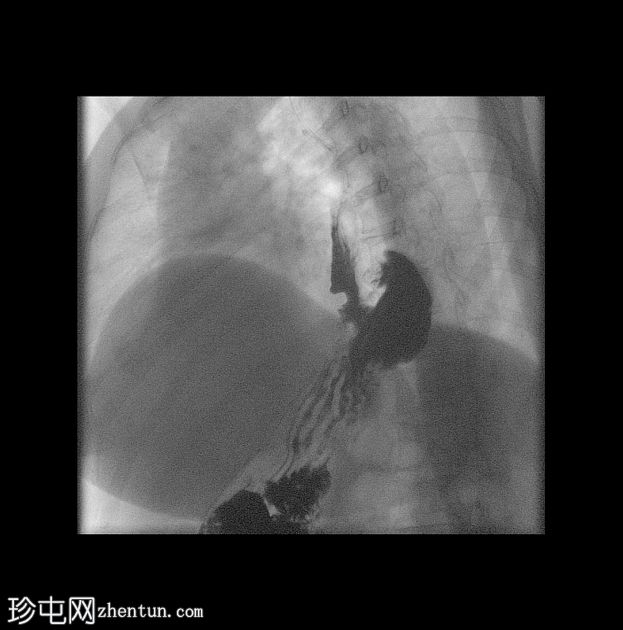

透视检查

左前斜位(LAO)

立位

斜位

仰卧位

胃食管交界处及胃底折叠术部位位于膈肌上方。

虹吸试验证实存在胃食管反流。